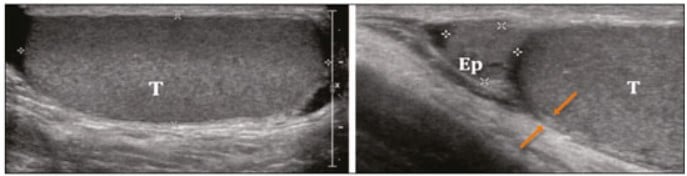

Torção do apêndice testicular

A torção do apêndice testicular é uma condição benigna em crianças, com torção de apêndices embrionários residuais. Este é um dos principais diagnósticos diferenciais da torção testicular, pois a mesma é uma emergência urológica necessitando de cirurgia imediata e o apêndice não.

Geralmente é uma clínica de dor localizada, com sinal do “blue dot” ou sinal do ponto azul. Este sinal, apesar de identificar a torção do apêndice testicular, só está presente em 20% dos pacientes.

Na USG observamos um apêndice hipoecoico com calcificação. Além disso, há presença de ssimetria com o apêndice testicular contralateral um bom parâmetro comparativo. No Doppler há pouco ou nenhum fluxo sanguíneo. Mais importante, não haverá alterações do testículo ipsilateral, afastando o diferencial de torção.